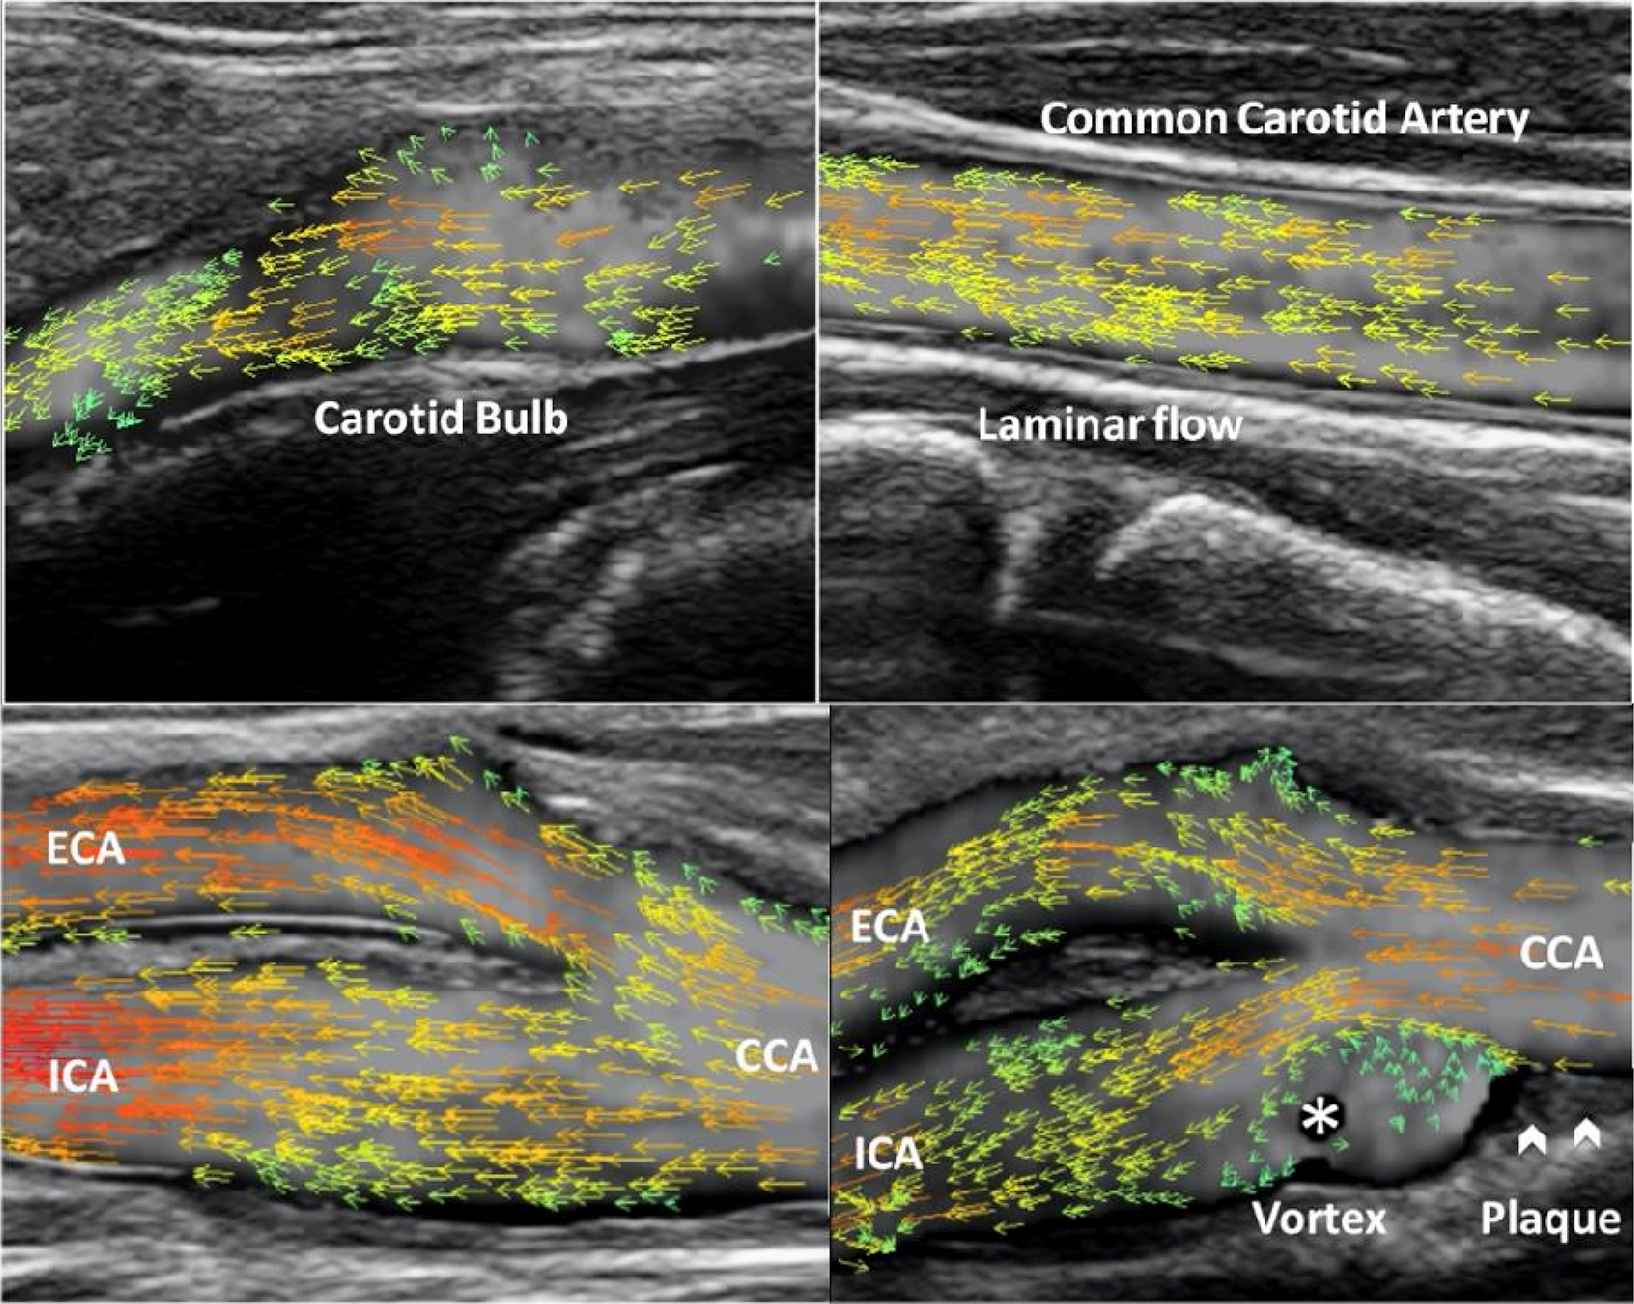

Hemodynamics becomes extremely complicated when plaques develop in the carotid bulb. The dynamic display with velocity vectors assesses flow patterns, e.g. laminar flow, vortex and turbulence (Examples are shown in the figure). The circular variance for the angles of vectors in a desired region of interest can be calculated, allowing disturbance quantification for the non-laminar flow. The method is capable of measuring volume flow (VF) and wall shear stress (WSS) at different locations. To ensure the accuracy both VF and WSS are calculated based on a frame rate of 400–600 Hz and vector velocities.